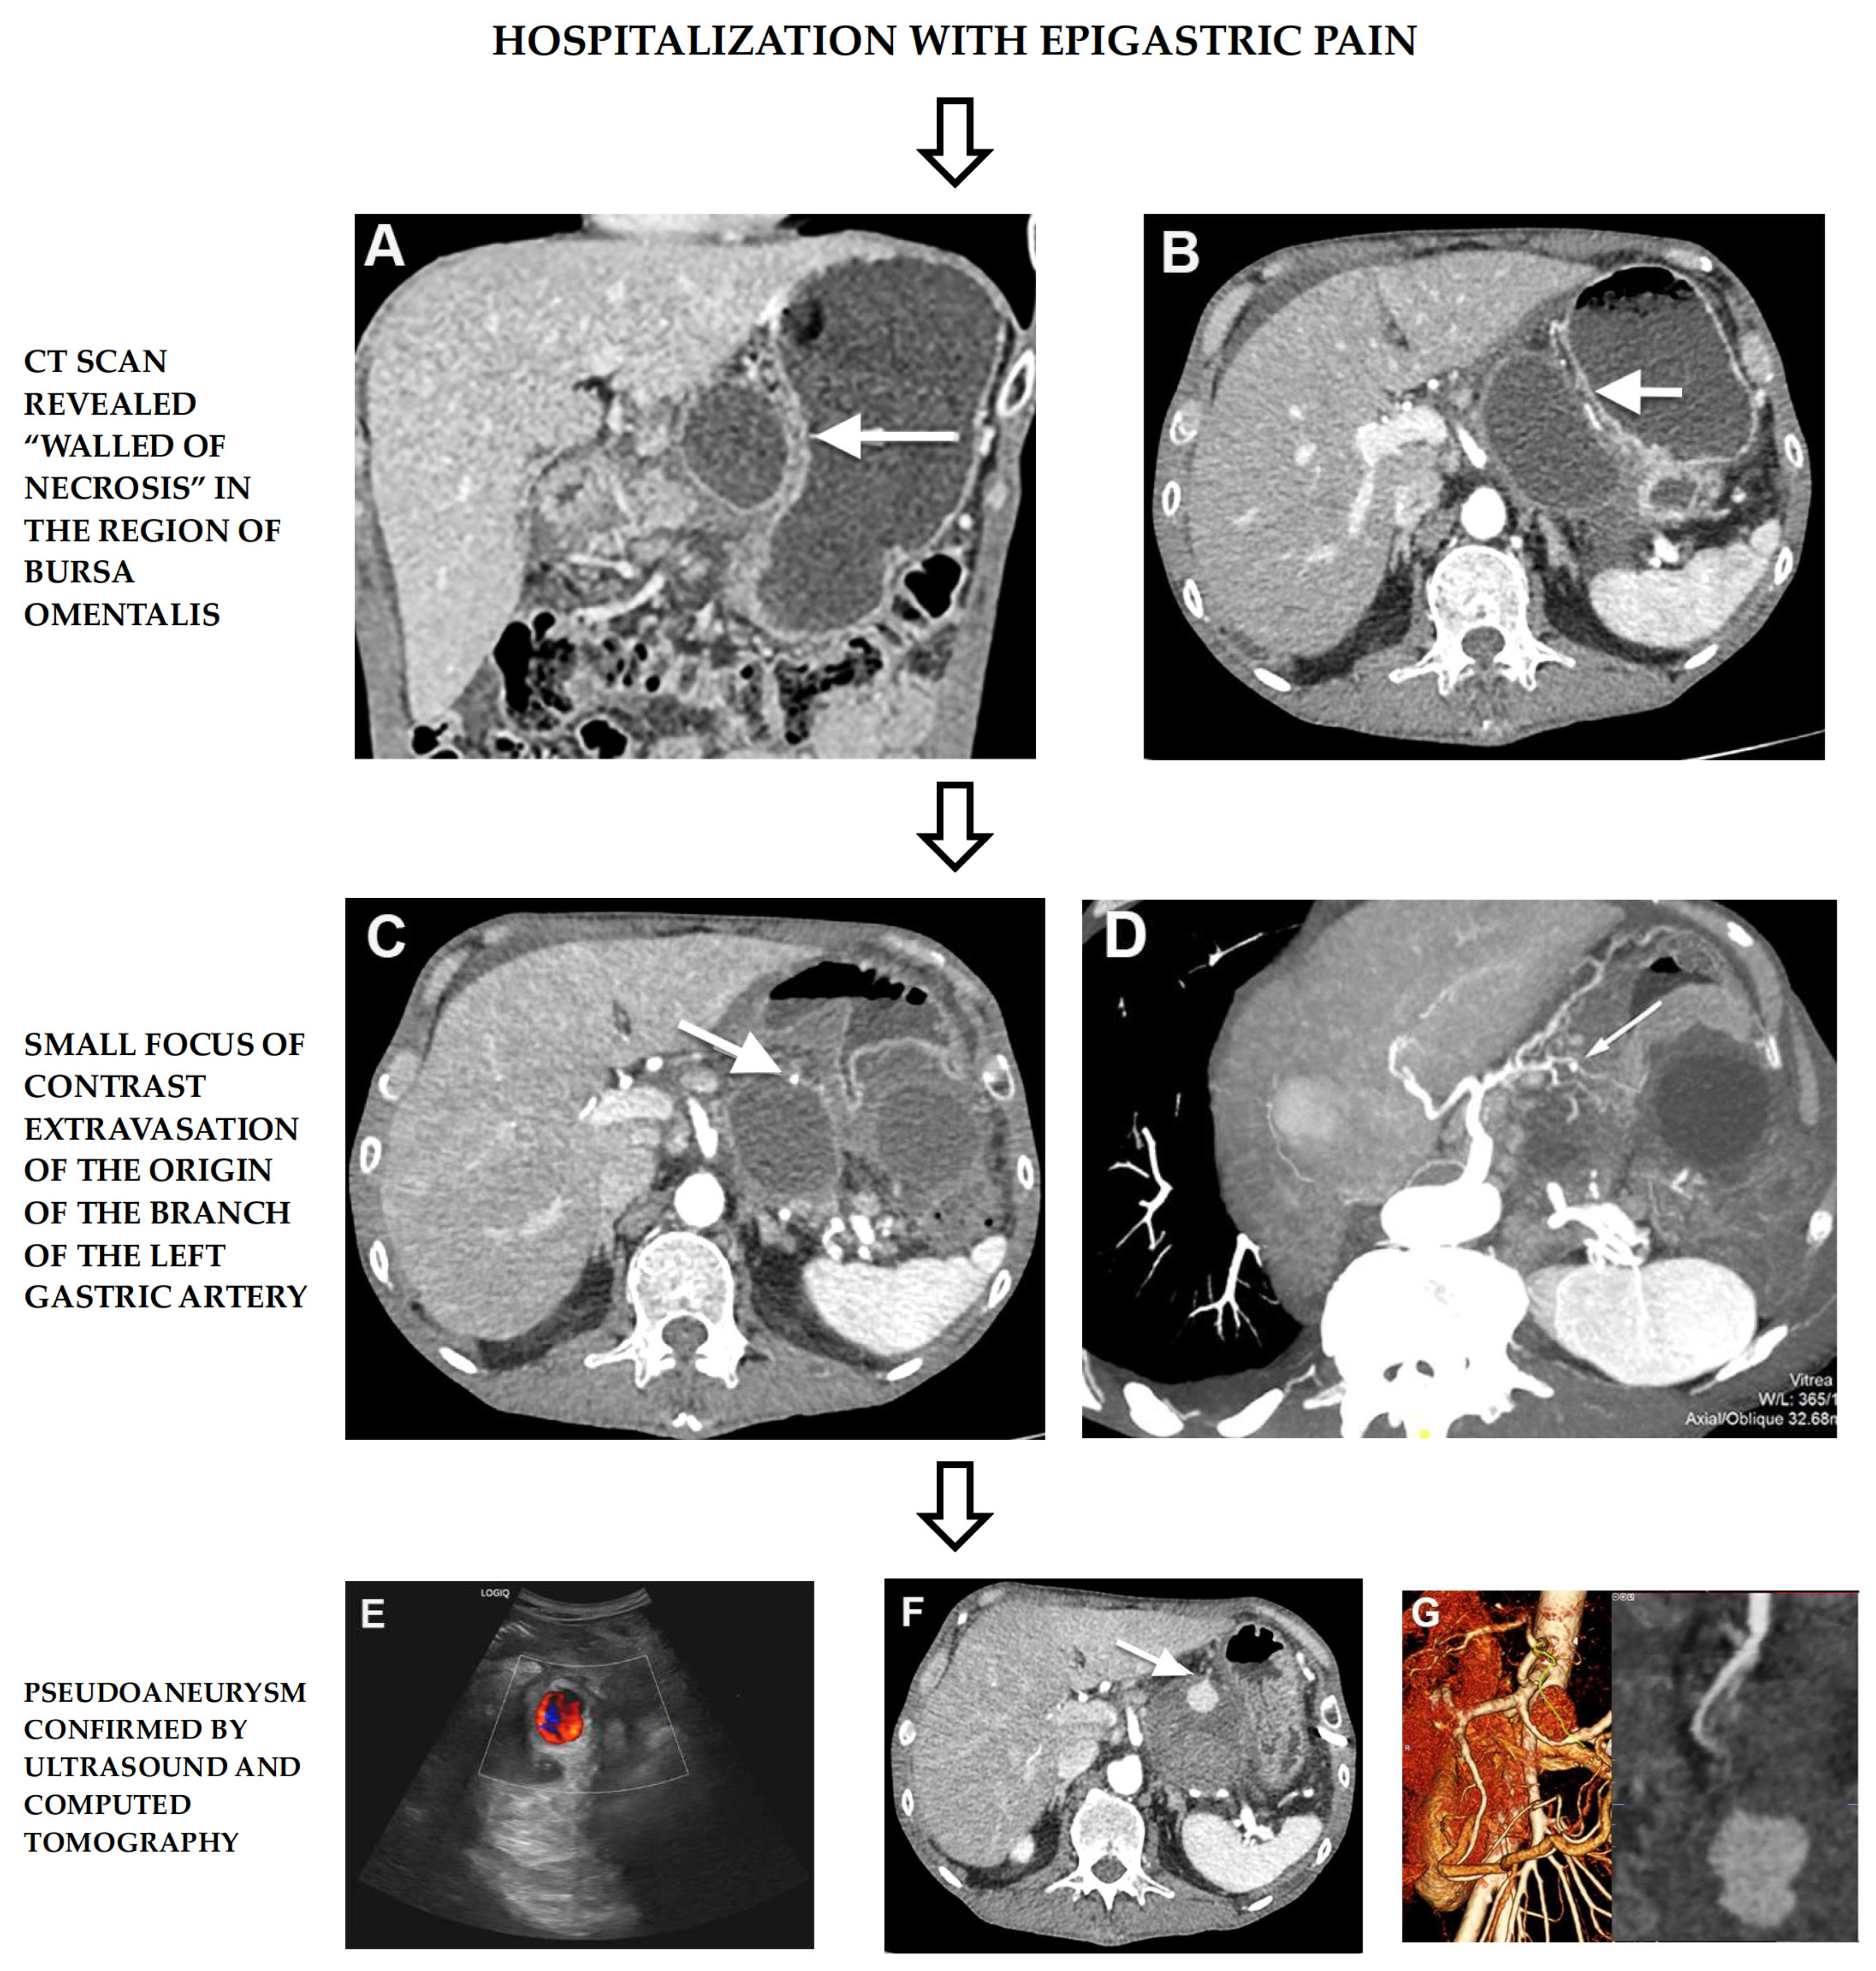

2. Case Report